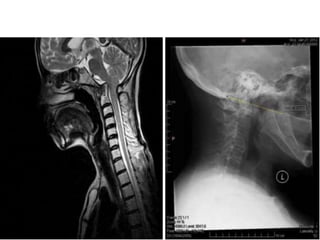

Arnold-Chiari Malformation

• Type 1- m/c -caudal displacement of peglike cerebellar tonsils

below the level of the foramen magnum, -congenital tonsillar

herniation, tonsillar ectopia, or tonsillar descent.

• Syringomyelia in 50 to 70%.

• Type II -less common and more severe, almost invariably

associated with myelomeningocele. Symptomatic in infancy or

early childhood. -caudal displacement of lower brainstem

(vermis, medulla, pons, 4th ventricle) through the foramen

magnum.